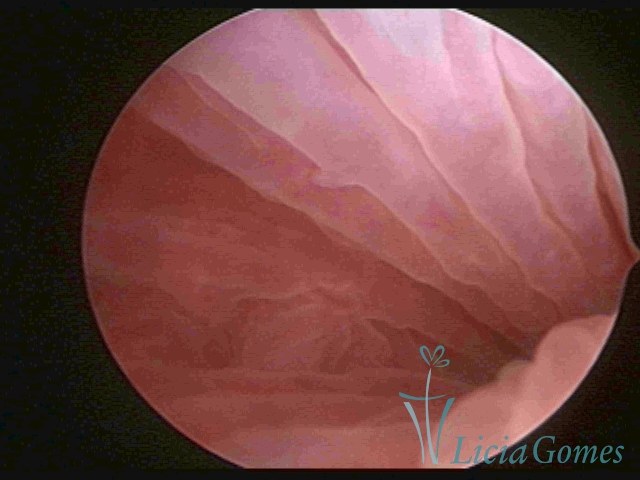

First part or proximal section or lower section:

During the proliferative phase, a light, crystalline mucus with a low adherence to the scope is found. The crypts and buds are a little swelled and vascularized, microvesicular, resembling grape clusters.